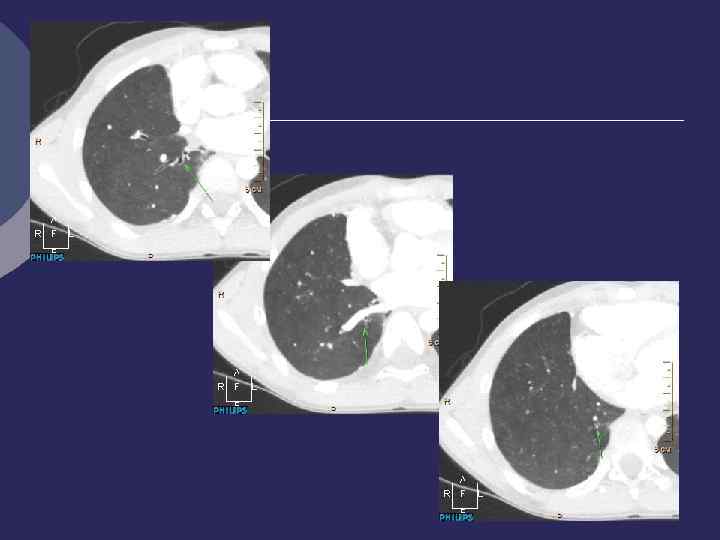

Гамартохондрома КАЛЬЦИНАТЫ

Гамартохондрома без кальцинатов (киста? )

КТ: гамартохондрома Контрастирование: отсутствие связи с сосудами, волнистые контуры

Ретгенологические признаки гамартохондромы Ø Правильная форма Ø Четкие гладкие или волнистые контуры Ø Средняя интенсивность Ø Включения извести (глыбки, слоистость, инкрустации) Ø Окружающая легочная ткань не изменена Ø Бронхи, сосуды огибают образование